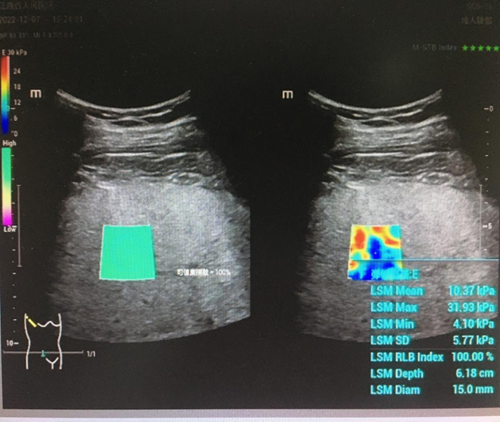

超声检查是公认的首选检查,是进行脂肪肝诊断、分型的最佳手段,同时需要检查肝功能。当肝功能异常,谷丙转氨酶(ALT)偏高时,可做肝脏超声弹性成像来评估肝纤维化的程度。

超声弹性成像技术作为新型医学影像与生物力学相结合的诊断技术,以其无创、简便、实时可视化、定量评估肝脏硬度等优势,通过测量肝脏弹性指标评估肝纤维化程度,定量诊断肝纤维化,已逐步应用于临床。